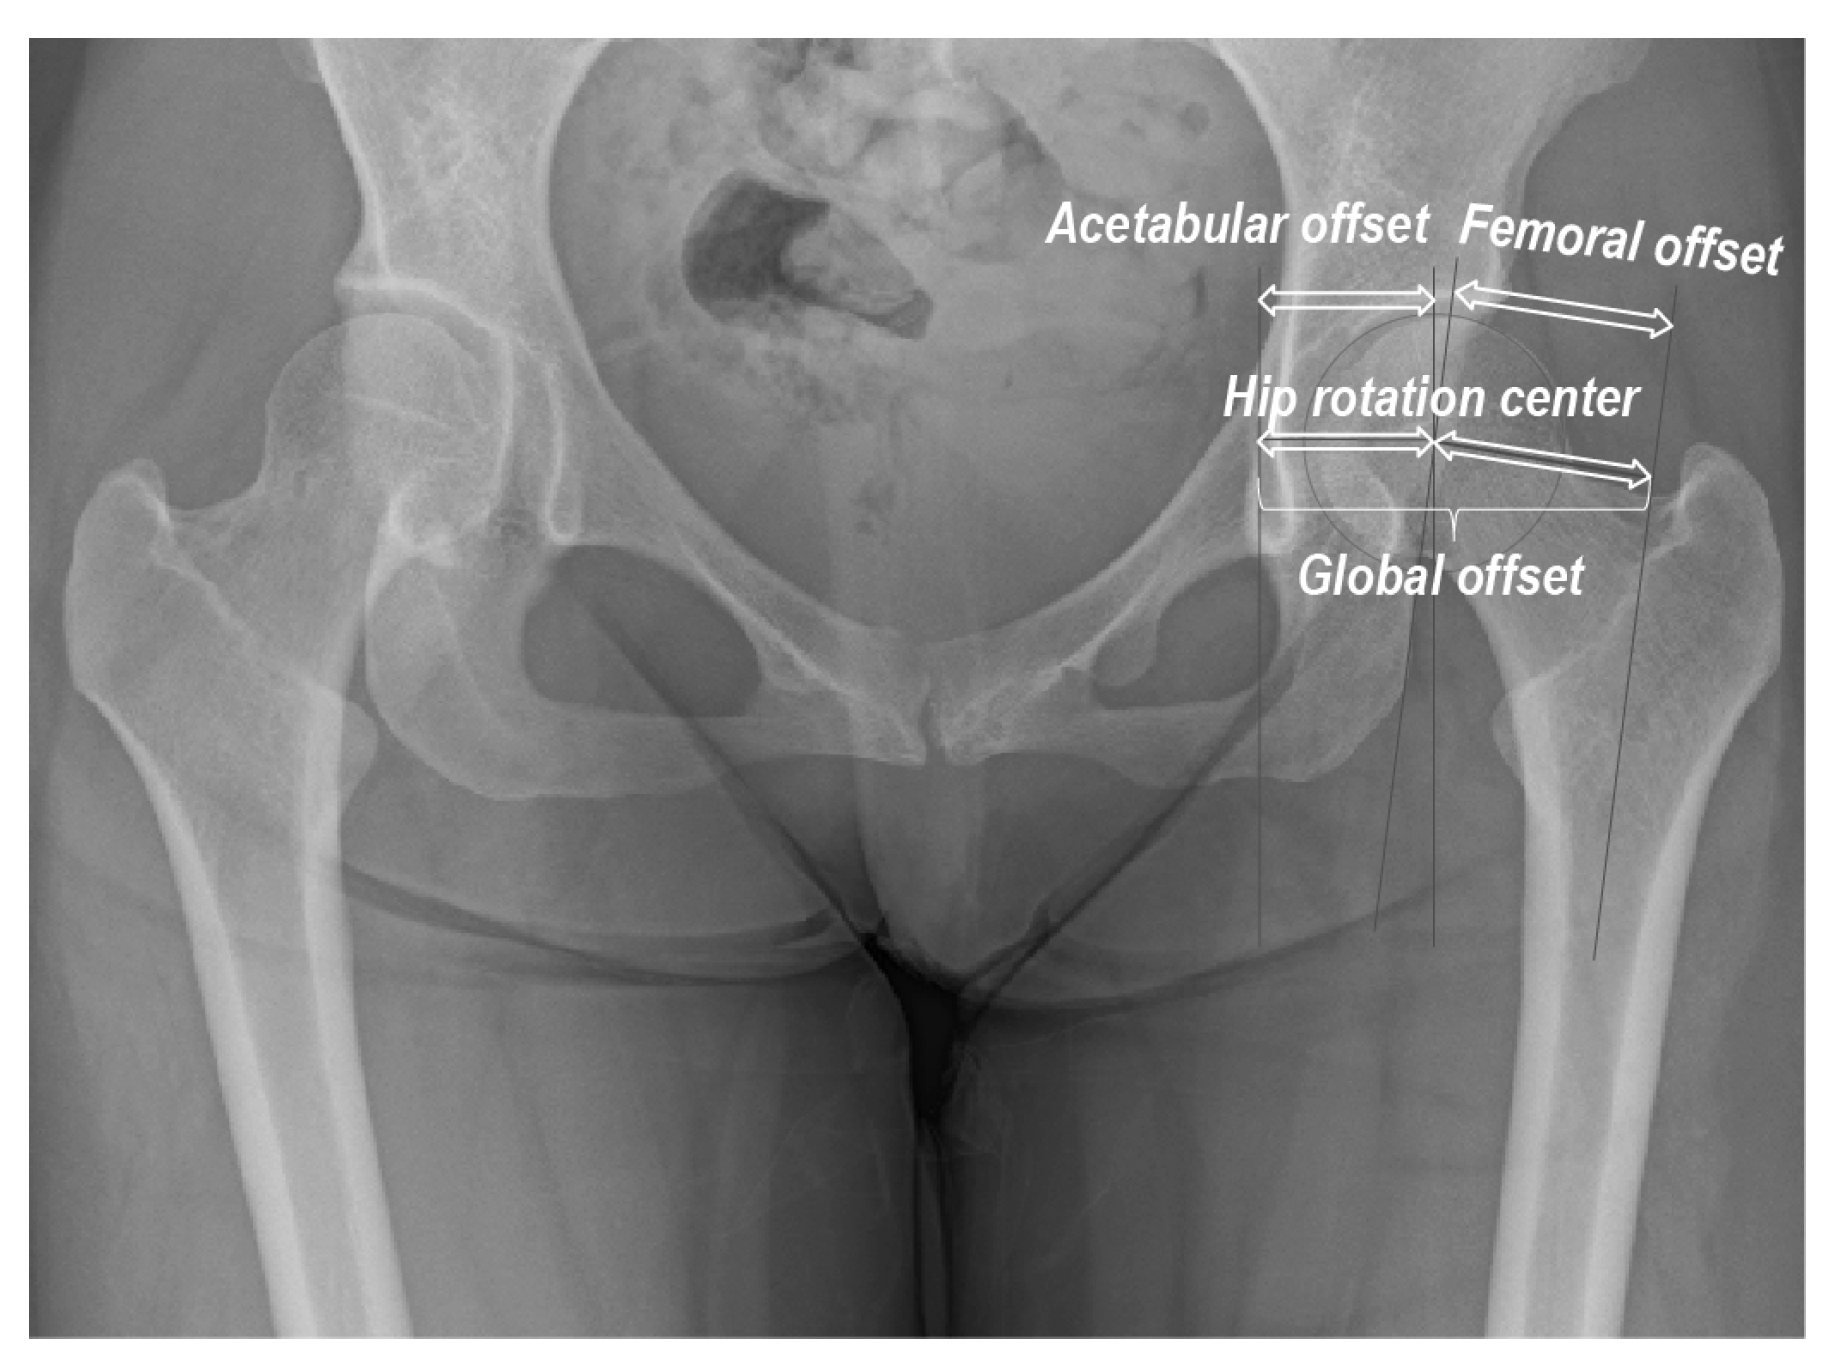

| Global offset (mm) | 80.9 (8.8) | 72.6 (5.9) | <0.001 |

| Acetabular offset (mm) | 37.7 (4.0) | 34.2 (2.4) | <0.001 |

| Femoral offset (mm) | 43.2 (8.3) | 38.4 (5.0) | 0.005 |